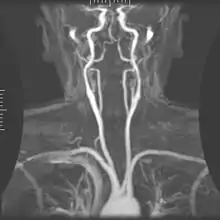

Angiography

Magnetic resonance angiography (MRA) generates pictures of the arteries to evaluate them for stenosis (abnormal narrowing) or aneurysms (vessel wall dilatations, at risk of rupture). MRA is often used to evaluate the arteries of the neck and brain, the thoracic and abdominal aorta, the renal arteries, and the legs (called a "run-off"). A variety of techniques can be used to generate the pictures, such as administration of a paramagnetic contrast agent (gadolinium) or using a technique known as "flow-related enhancement" (e.g., 2D and 3D time-of-flight sequences), where most of the signal on an image is due to blood that recently moved into that plane (see also FLASH MRI).[51]

Techniques involving phase accumulation (known as phase contrast angiography) can also be used to generate flow velocity maps easily and accurately. Magnetic resonance venography (MRV) is a similar procedure that is used to image veins. In this method, the tissue is now excited inferiorly, while the signal is gathered in the plane immediately superior to the excitation plane—thus imaging the venous blood that recently moved from the excited plane.[52]